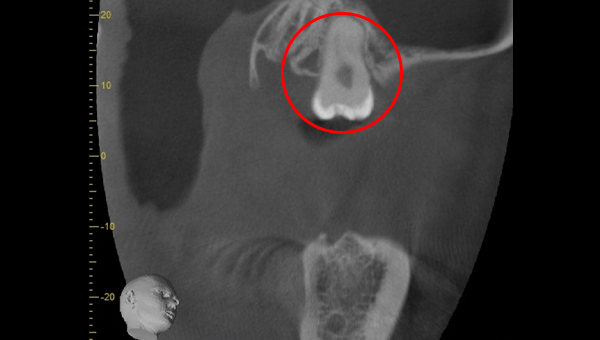

CT画像

骨の状態はそこまで悪くないが、欠損が大きい。